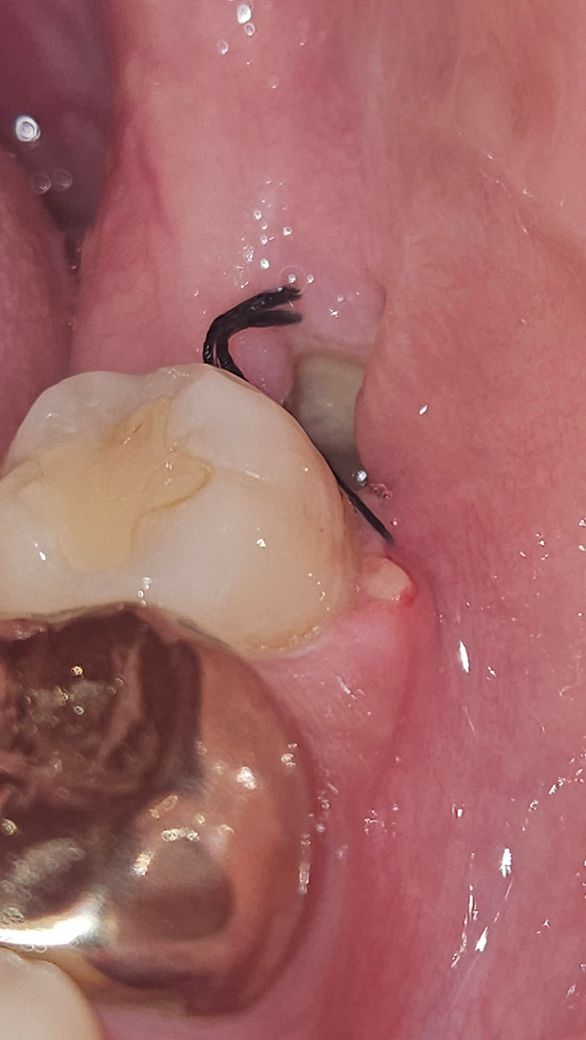

사진은 저게 최대고, 발치 구멍이 작은건지 안까지는 빛을 비춰도 잘 보이지 않네요. 드라이소켓 전조증상이 있을까요? 사진을 봤을 때 드라이소켓일 가능성이 높은가요? 앞에 구내염 때문에 이렇게까지 아플 수가 있나요? 만약 드라이소켓이라면 치료 방법은 무엇이고 치료의 고통 정도는 어느정도일까요?

• 1번 째 사진